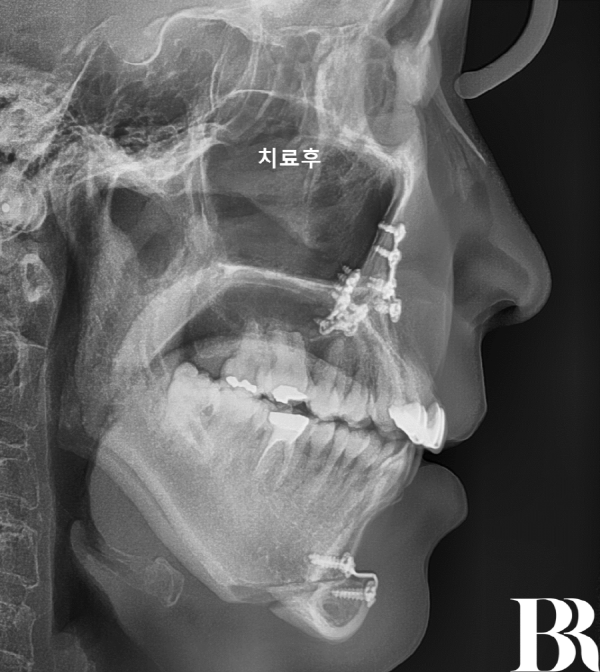

수술직후 옆에서 찍은 엑스레이 : 주걱턱 이미지가 많이 개선되었다.

그래서 선수술 -> 수술 후

인비절라인을 활용하는 교정으로

진행하게 되었습니다.

-> '양악수술' 환자 중에서도

50대는 외모 변화시점이

특히 중요하므로 선수술이

강력 추천되는 케이스였습니다.??

*선수술은 경험이 필수”

치료 전, 후 정면 모습 : 수술부터 교정까지 약 1년 정도의 기간이 소요

수술 날짜 : 2024년 9월

교정시작 날짜 : 2024년 11월

교정종료 날짜 : 2025년 11월

교정 장치 : 인비절라인 3년형

치료 방법 : 선수술 + 후교정